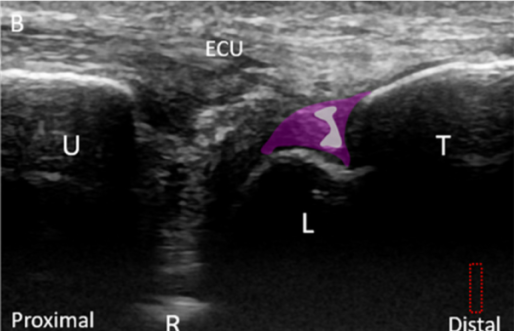

@ DOI: 10.3390/jcm8101540

관절 연골 외에도

반월 연골 유사체가 손상되거나**

월상 삼각 인대가**

함께 파열된 환자분들도 있고요.

만성기 환자 대부분은

손목 관절염도 동반하고 있습니다.**

병명은 모두 TFCC 손상이지만

개인별로 상태가 모두 다르니사실상 똑같은 병이 아닌 겁니다.